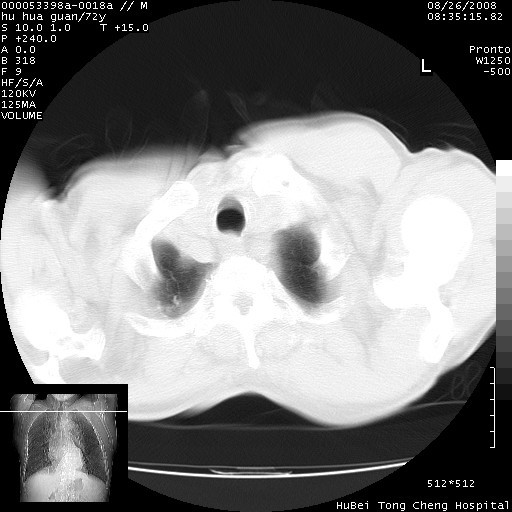

标题: CT15582:M,72Y。请老师帮分析胸部病变。 [打印本页]

标题: CT15582:M,72Y。请老师帮分析胸部病变。

可以明确的说。肯定不是主动脉夹层破裂出血!考虑为淋巴瘤或间叶组织来源的恶性肿瘤可能性大。右肺小结节建议薄层观察,如能发现恶性征象,那椎前改变就考虑为转移所致。至于双侧少量胸水乃静脉血回流受阻所致。

图像及窗宽窗位均不理想。周围性肺癌/胸腔积液/纵隔积液。

1、右肺周围性肺癌、胸腔积液(双)

2、建议食道吞钡和增强检查排除食道和主动脉病变

3、后纵隔淋巴类肿瘤

1、右上肺结节病变,肺泡癌不除外,请随诊;左下肺近后纵隔病变,考虑纵隔型肺癌侵犯大血管可能;

2、右下肺背段少许炎症,双侧胸腔积液,右下肺纤维索条。

降主动脉前移位,后纵隔占位

后纵隔占位,降主动脉前移位;双侧胸腔积液;应排外食管病变侵犯血管可能;